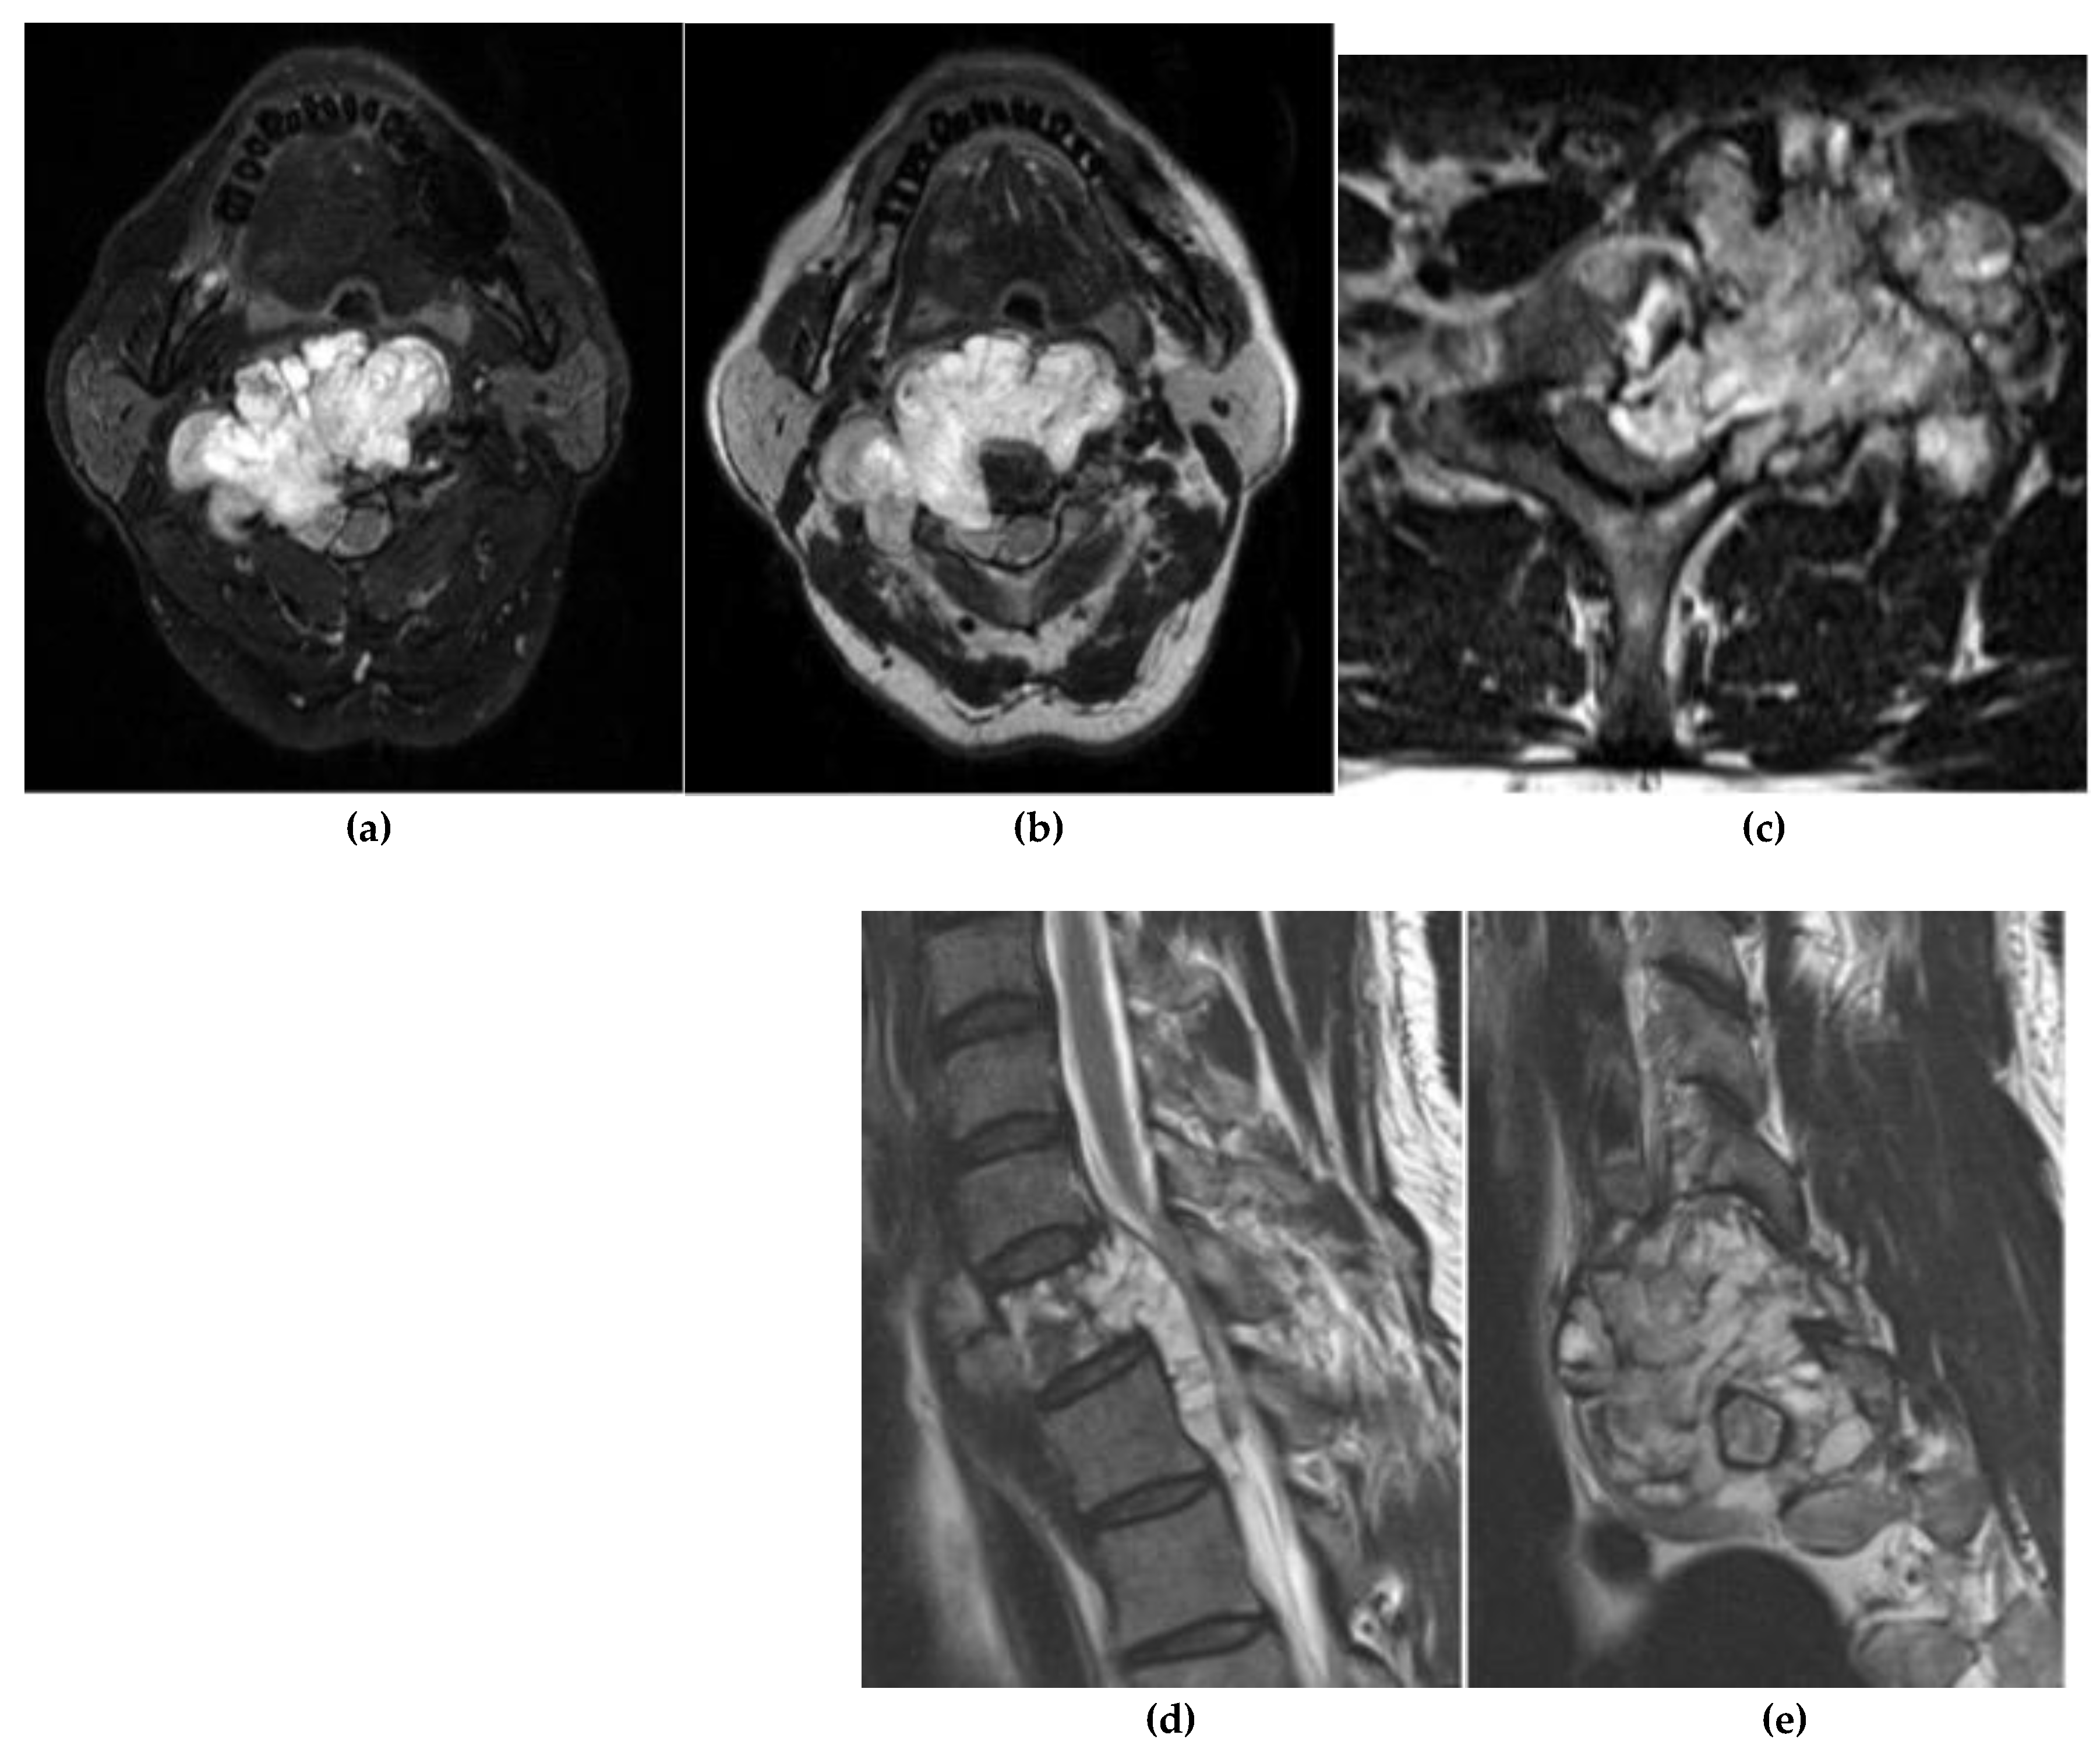

Chordoma

- Lee, S. H. , Kwok, K. Y., Wong, S. M., Chan, C. X. J., Wong, Y. T., & Tsang, M. L. Chordoma at the Skull Base, Spine, and Sacrum: A Pictorial Essay. J. Clin. Imaging Sci. 2022, 12, 44. [Google Scholar] [CrossRef]